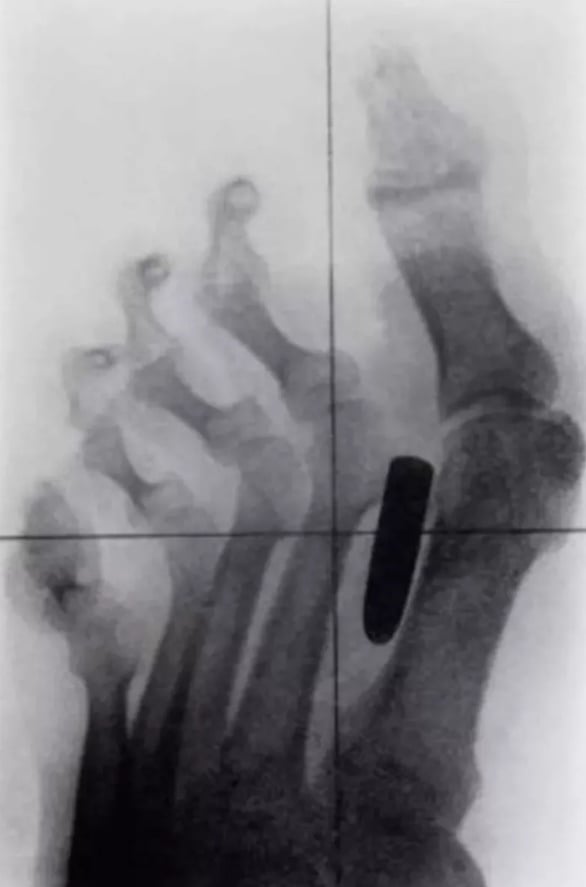

Orta parmağına çivi saplanmış bir hasta...